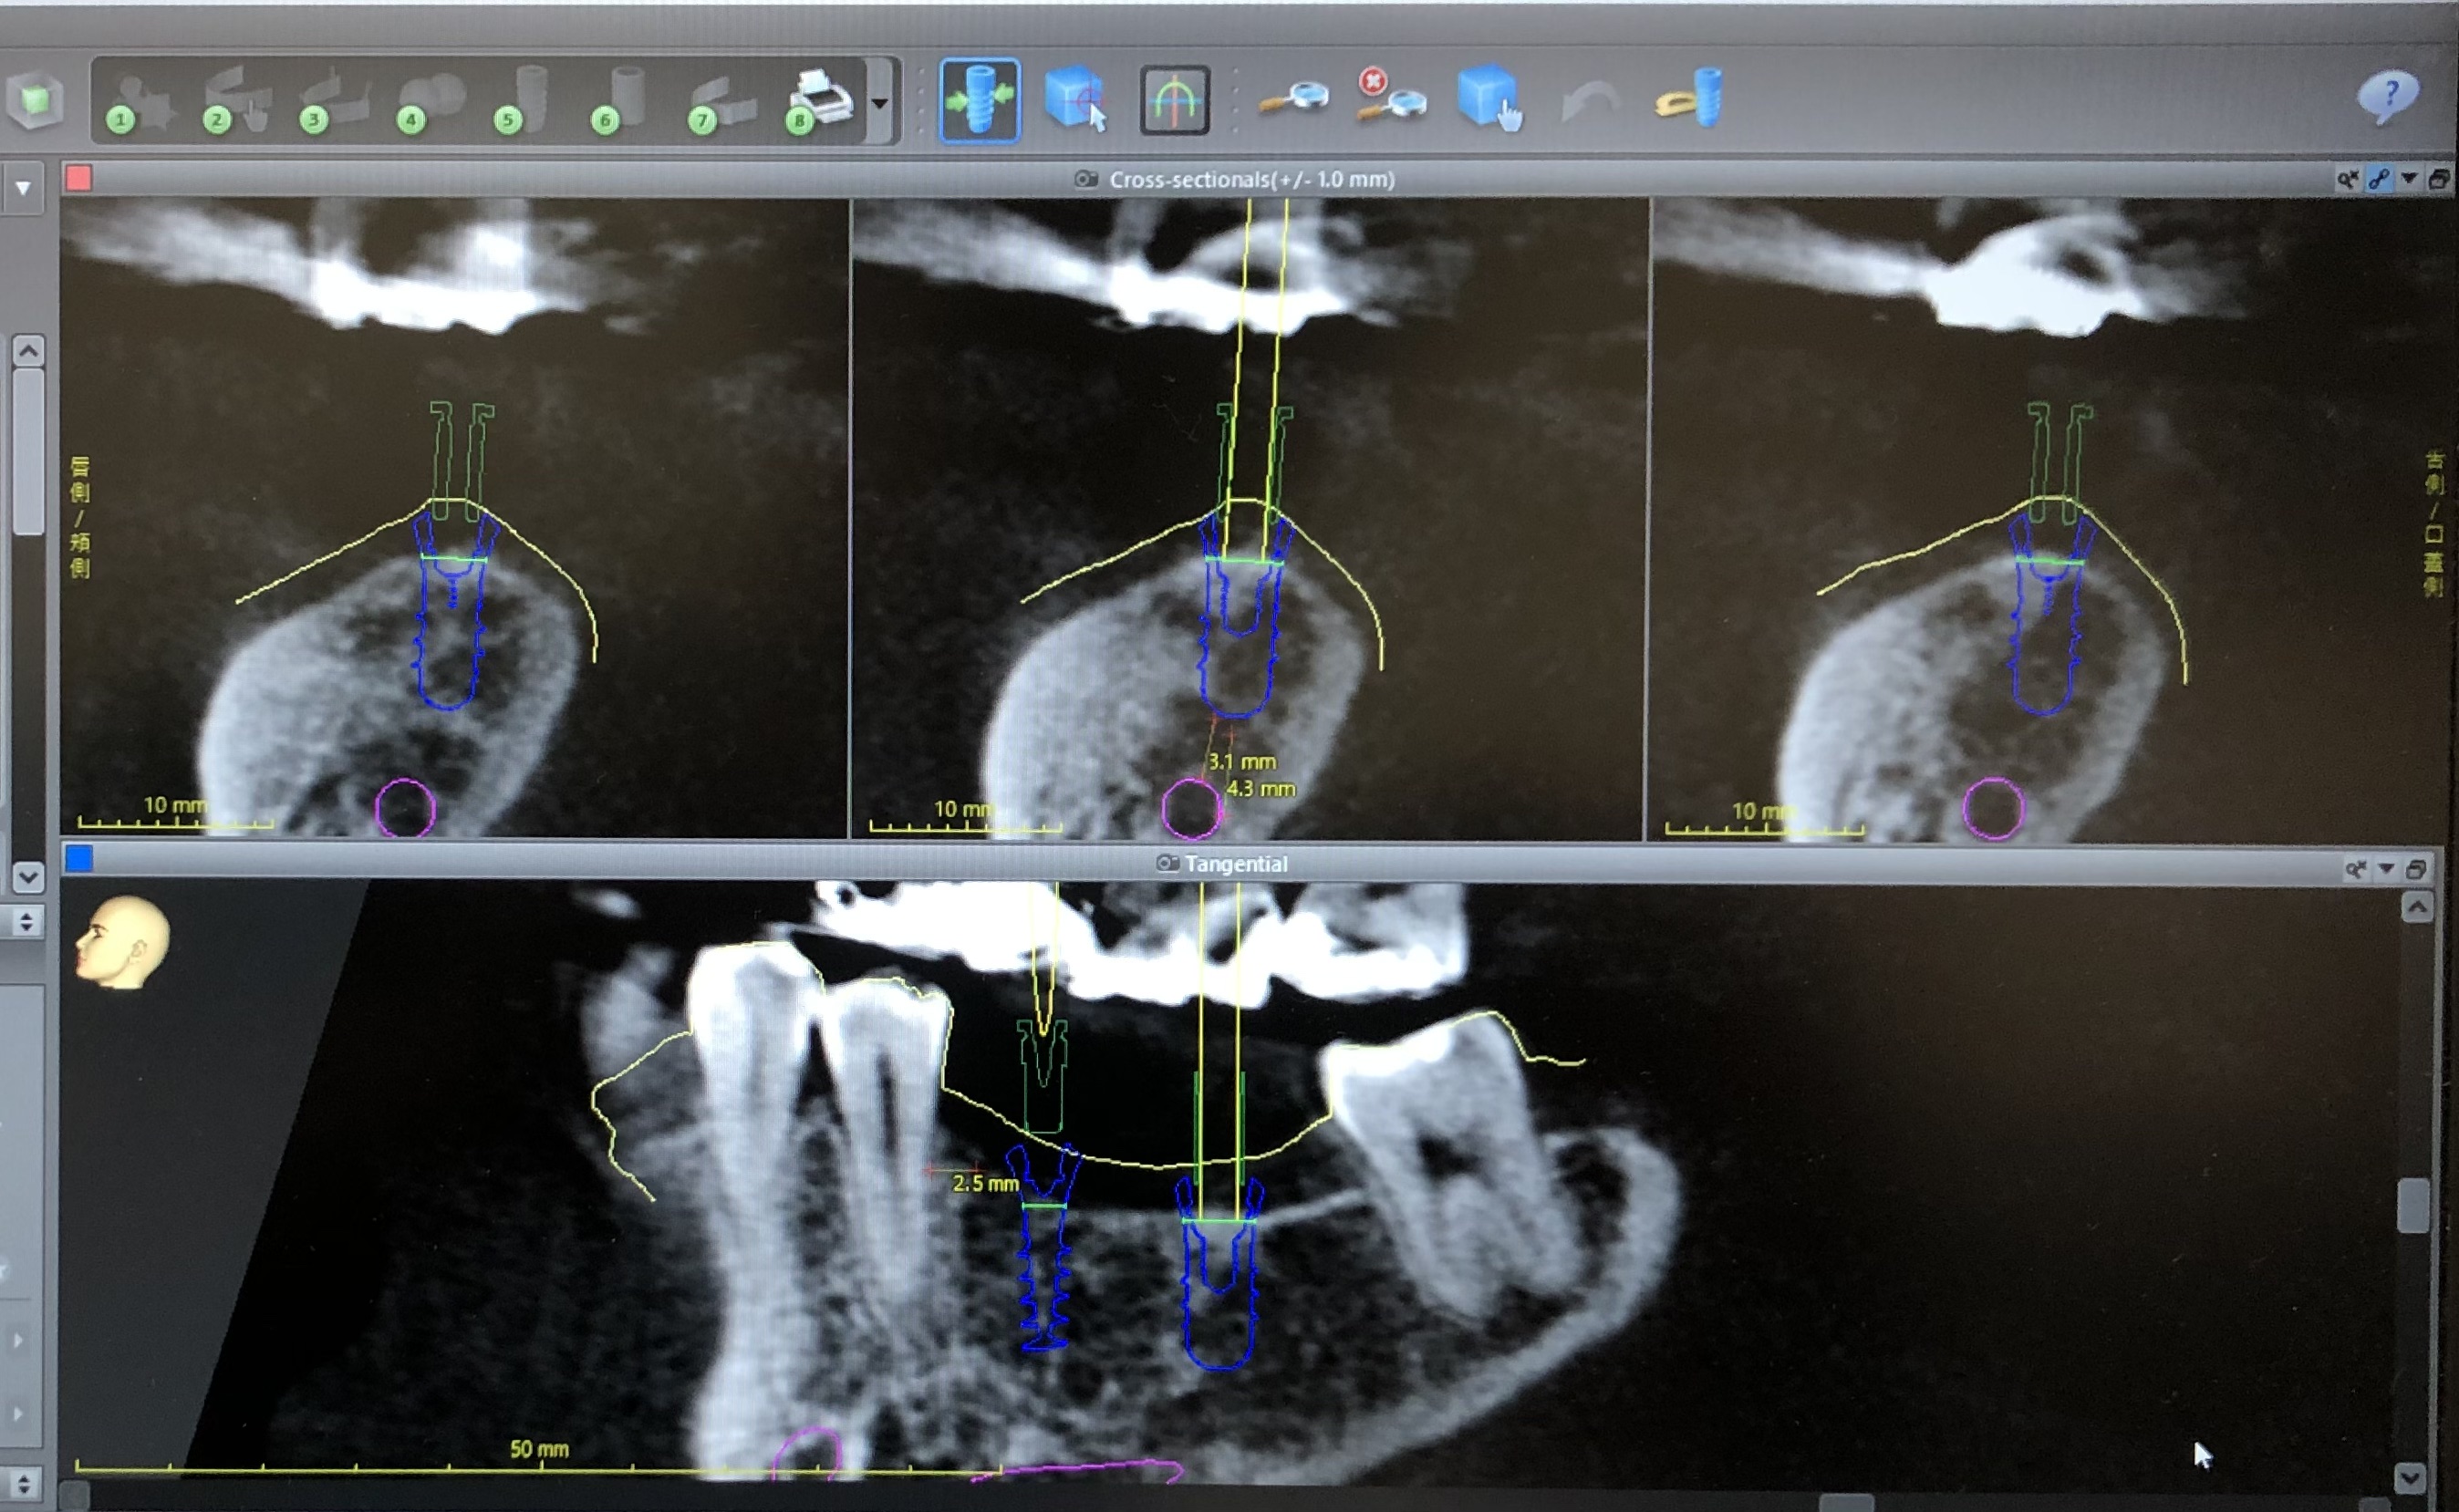

CTと口腔内スキャンのデータと専用のソフトウェアを用いて、コンピュータ上でインプラント治療を計画した後、手術用のガイドを作製し、ガイドを用いてインプラント手術を行います。

これにより、計画通りの位置にインプラントを埋入することができ、より安全で正確な治療を行うことができます。

インプラントが理想的な位置に埋入されれば、機能性や審美性に優れた人工歯の作製が可能になります。

*ガイドを使用することにより、歯肉を切開しない治療(フラップレス手術)が可能になることもあります。